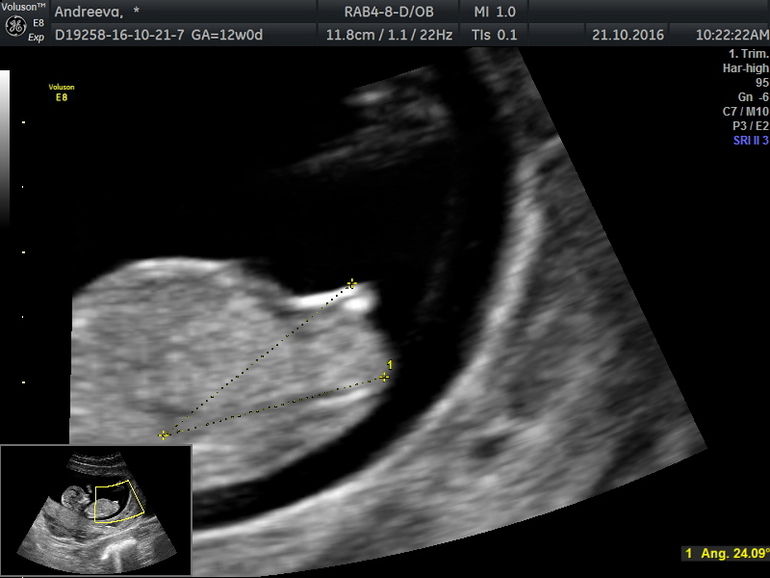

Кто разбирается в бугорках?

Вот нашла фото бугорка) мне по это фотке на 11+5длктор обещала парня)а сейчас говорит девочка

Я тоже больше к девочке склоняюсь .У нас мальчик и у нас перчик торчал кверху с 13 недели ))В 19 подтвердили. А вы сами кого хотели или без предпочтений?)